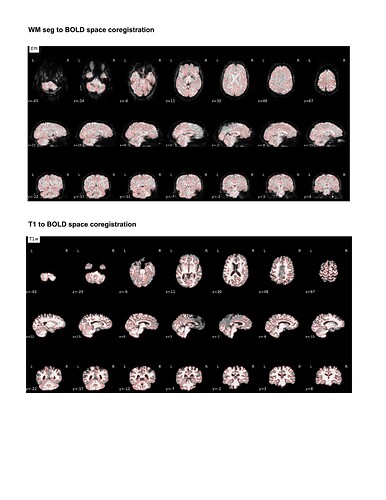

For my dataset I have found that ANTspyNET consistently produces a good/clean brain mask compared to fmriprep (antsBrainExtraction x Freesurfeer method). The default fmriprep method often outputs brain mask/segmentations that include the skull/non-brain tissues. As a result, I have been feeding my ANTspyNET mask as input via the --derivatives flag. While this works and the resulting outputs look good (see attached screenshots: decent tissue segmentations, good BOLD-T1 coreg etc), I noticed that the preprocessed anatomical T1 gets skull stripped in the process. Is this a sign of something going wrong under the hood?